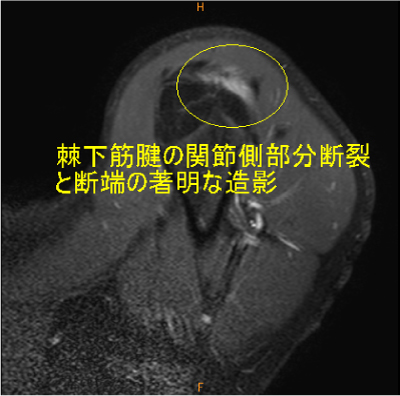

肩甲下筋腫瘍(デスモイド), 棘上・下筋腱関節側部分断裂

![]() |